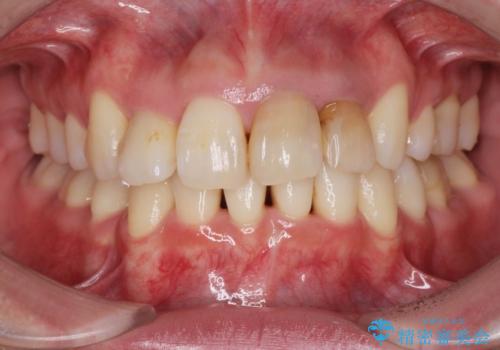

- 52.8万円(ジルコニアクラウン×4・仮歯×4)費用は治療当時の料金となります

自然な歯の色に仕上げることができ、大変喜んでいただくことができました。